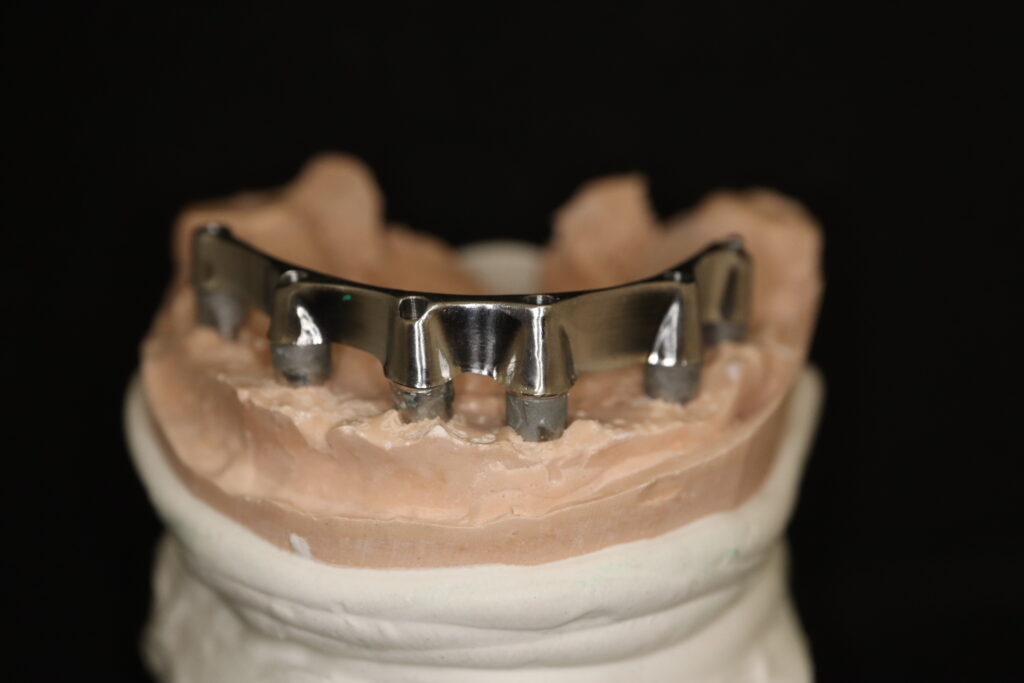

На консультации было принято решение о перепротезировании протезом из диоксида циркония на титановой балке.

Спустя 27 дней был зафиксирован протез с опопрой на дентальные имплантаты из диоксида циркония с каркасом из титана.